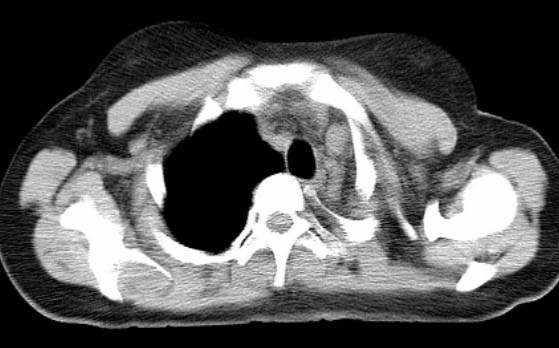

标题: CT25648:求教:是肺发育不全还是结核?

女  20岁。一月前咳血,诊“肺结核”抗痨治疗一月后,咳血停止,现复查。病人精神好。前后ct片对比未见明显变化。既往体检“正常”

1)考虑左肺结核并肺不张、支气管扩张。2)纵隔疝。

以前体检正常只能考虑左肺结核并肺不张、支气管扩张。2)纵隔疝。

考虑左肺结核,左肺毁损,纵膈左偏,既往体检正常不可靠,tb一个月也不会这个样子的,有钙化,应该病程较长,冰冻三尺非一日之寒!

左肺发育不全。

考虑左肺结核,左肺毁损,纵膈左偏,既往体检正常不可靠,tb一个月也不会这个样子的,有钙化,应该病程较长,冰冻三尺非一日之寒

结核,左肺毁损。